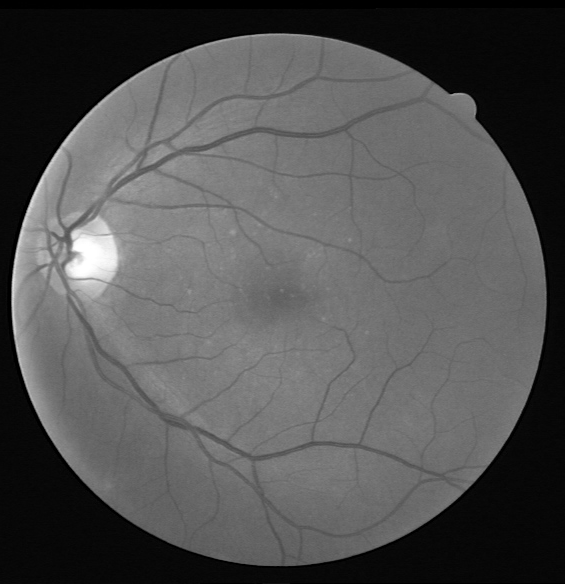

Figure 7: Visual results for two sample DRIVE images.

Results for DRIVE Test Images: Quantitative results of BLCB-CNN for all DRIVE images are computed, which shows that the proposed method achieves an average accuracy of 96.22. The average sensitivity/specificity value of 81.57/97.65 also indicates the model’s ability to accurately segment vessel pixels (including thin vessels). The AUC results are also consistent with the accuracy obtained for all the images. Figure 7 demonstrates the visual outcomes for two sample DRIVE images. It can be observed that the proposed method segmented both thin and thick vessels much closer to ground truth binary masks. This is further evident from the focused rectangular areas of the output/ground-truth images.